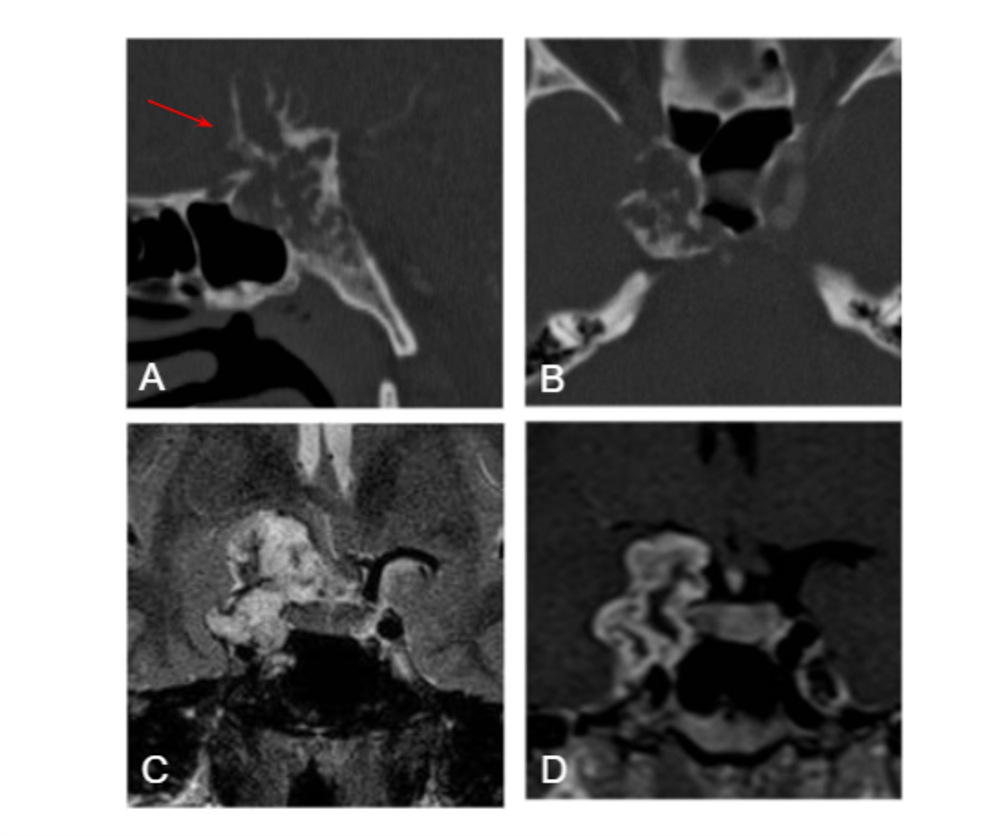

Figura A y B. TC craneal sin CIV en plano sagital (A) y axial (B): Lesión en región paraselar derecha con calcificaciones en forma de “arcos y anillos “ (flecha) que produce osteolisis del clivus.

Figura C. RM cerebral T2 coronal: Lesión hiperintensa con imágenes lineales hipointensas que representan las calcificaciones.

Figura D. RM cerebral T1 coronal con gadolinio: Masa con realce periférico en estrecho contacto con el quiasma óptico y la arteria carótida.